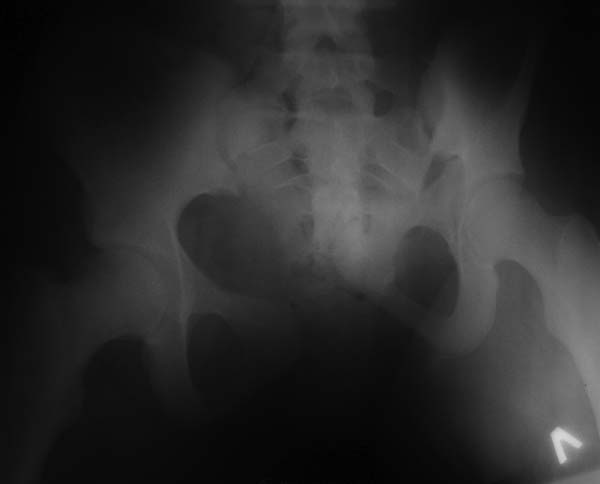

Девочка 14 лет. Кататравма (падение с высоты 4-5 этажа). Вертикально нестабильный перелом таза со смещением, разрывом лонного и левого подвздошно-крестцового сочленения, перелом крестца, открытый перелом костей голени. Ребёнок оперирован на 10-е сутки после травмы - выполнили максимально возможную репозицию на ортопедическом столе, синтез лонного сочленения реконструктивной пластиной (из имеющихся пластин - на 7 дыр - самая длинная, получилось только по 2 шурупа с каждой стороны, поэтому пришлось подстраховаться проволокой), АВФ. Задний комплекс не фиксировали ввиду отсутствия канюлированных (да и неканюлированных)шурупов должной длинны.В настоящий момент перед нами стоит вопросов:1. Обязательно ли фиксировать подвздошно-крестцовое сочленение, либо фиксации АВФ будет достаточно? Аппарат стоит достаточно стабильно, девочка при перемещениях в пределах постельного режима болевых ощущений не испытывает.2. Что делать с отломком крестца, который довольно значительно смещён кпереди? В настоящий момент никаких проблем с дефекацией у больной нет, хотя, глядя на КТ, создаётся впечатление, что отломок прямо-таки лежит на прямой кишке. Репонировать-фиксировать? Просто удалить? Вообще не трогать? Не создаст ли он в дальнейшем проблем во время родов?Хотелось бы знать мнение уважаемых коллег.Заранее спасибо.

Здравствуйте, Сергей! Нестабильный перелом типа С подлежит обязательной задней фиксации или илиосакральными винтами, или пластиной, или стяжкой (кто что лучше умеет и чем оснащен). Возможен циркулярный АВФ (Уральский НИИТО). В Вашем случае, при невозможности восстановления заднего комплекса,- постельный режим до 2-х месяцев. Учитывая недостаточную репозицию в крестцово-подвздошном сочленении в будущем девочка обречена на хронический болевой синдром. Может быть стоило выполнить репозицию отломков в аппарате, а вторым этапом делать погружной остеосинтез. Костный фрагмент, думаю, можно оставить. После такой травмы речь будет идти о кесаревом сечении, а не о родах естественным путем.

Это не частый случай в детской практике. Вы очень хорошо сопоставили и фиксировали переднее полукольцо. Крестцово-подвздошное осталось в приличном смещении. Прекрасно - что нет неврологической клиники. Сейчас больная лежит. Поэтому всё хорошо. Учитывая соотношение крестец-подвздошная кость - кажется, что первые же проблемы возникнут при попытке поставить больного на ноги. Разорваны важнейшие стабилизирующие и воспринимающие нагрузку связки в системе позвоночник-крестец-таз. В таком положении фрагменов их адекватное восстановление и последующее функционирование , как мне кажется, не возможно. В возрасте 14 лет это взаимоотношение критично. Я имею в виду отсутствие репозиции. появление нестабильности, по-видимому, будет неизбежно. Это моё маленькое скромное мнение. Всё же надо было начинать сзади. Именно с репозиции. Фиксацию, ИМХО, можно было бы на безрыбье временно сделать и спицами (например-с резьбой) интраоперационно. В идеале - с навигатором, чтобы не задеть крестцовый канал, или с пальцем, контролирующим положение отломков над гребнем подвздоной кости и "навигирующим" проведение спицы. Сейчас Вам это сделать помешает LCP, жёстко фиксирующая переднее полукольцо и смещенное положение отломков. АВФ не "прижмёт" подвздошную кость к крестцу, и не выполнит репозицию. Возраст больной, мне кажется, не простит в дальнейшем погрешность в положении костей и, чем дальше, тем труднее будет исправлять . Это только мнение и ничего личного.Прямая кишка здесь в меньшей степени заинтересована - это вовсем не главное. Вероятные роды в насоящей тактике лечения совсем не играют решающей роли. Всё же - как неврология?